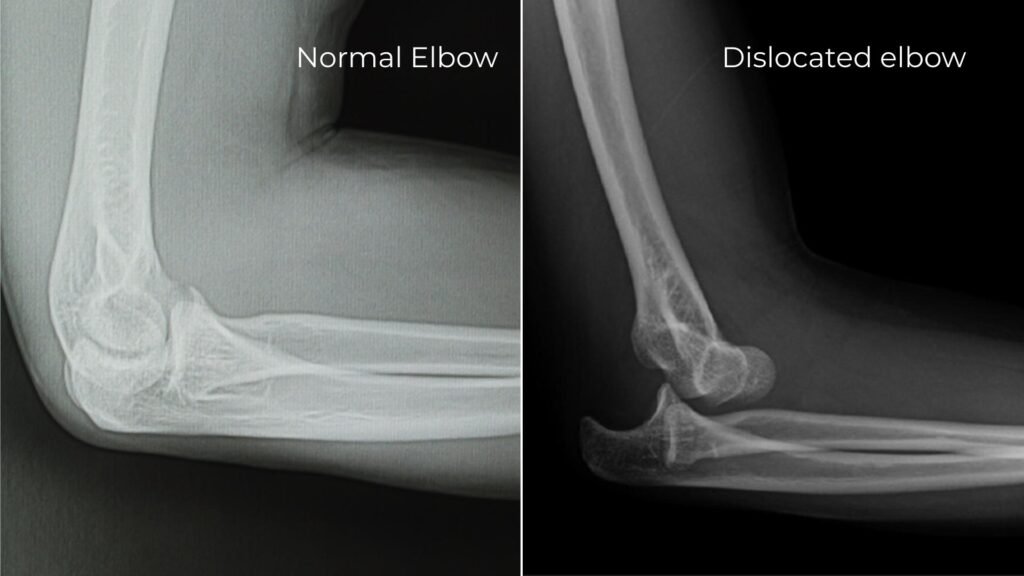

xray showing normal elbow compared to posterior dislocation of elbow

If you observe the X-ray, the one on the left is of a normal elbow joint, the one on the right is the elbow joint, where the elbow is dislocated, and it’s displaced posteriorly.